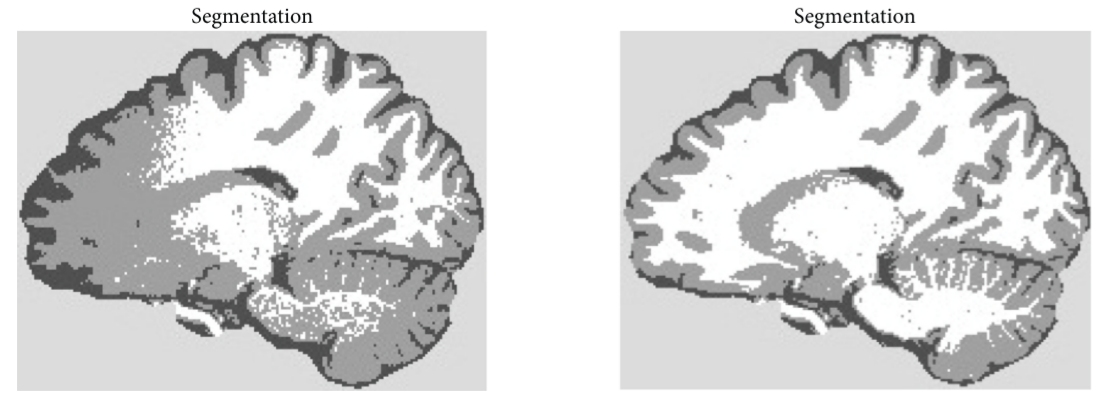

A bias field is a low-frequency signal which arises because of the fact that the magnetic field is not fully homogeneous inside the MRI scanners, but rather there are some small inhomogeneities, especially on the boundary of the scanner. If the image for the analysis is not preprocessed in a way to reduce the effects of the bias field, the performance of segmentation (and thereby all the later analyzing steps) is affected. Figure 3 shows the segmentation of the image with and without bias field removal.

To make the network adaptable to bias field effect, SynthSeg artificially modifies the training images, so that they act as if the effect were present. The modification is done in the following way: first, the low-resolution 4x4x4 matrix is sampled from a normal distribution with zero mean. Then, it gets upsampled to the resolution of the training image and exponentiated afterward (which ensures that all the values of the matrix are positive). Finally, the image is multiplied with the matrix

Fig 3. The comparison of the segmentation with and without the presence of bias field. Image source: [5]